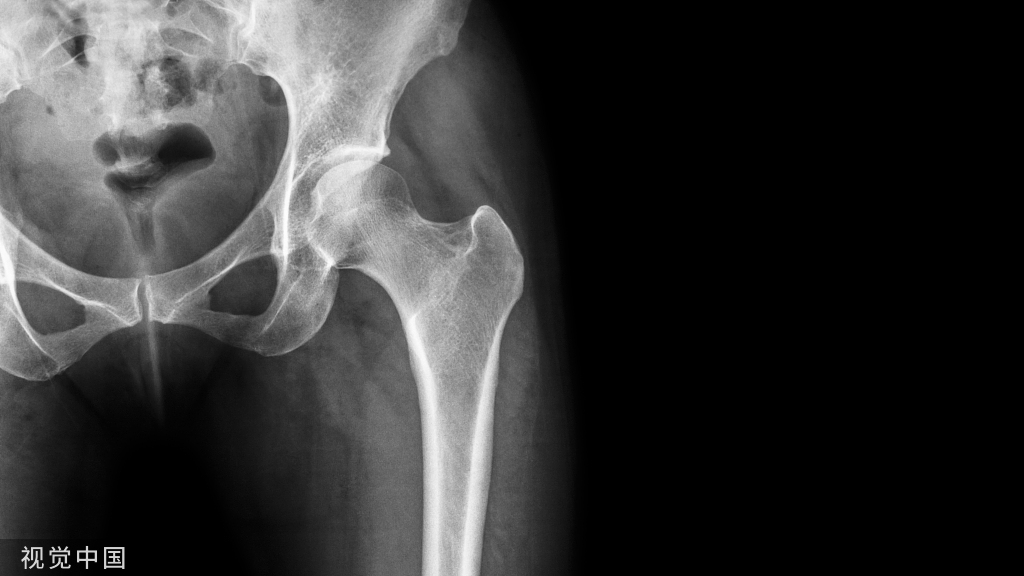

(一)缝线的标记与大结节的固定

由于肱骨近端骨折多为中老年患者,其骨质较差,故在术中探查常可见肱骨大结节粉碎。此时可在显露骨折后内旋肩关节,探查肩袖,再使用不可吸收缝线。自肩袖的腱性部分与大结节骨折片接合部缝合标定。标定后可使用该缝线牵引骨折片,以利显露。在骨折复位后,标记的缝线可通过钢板上预留的孔道打结固定以增加固定的稳定性。在此需要强调的是,有时肱骨大结节粉碎,部分骨折片向后内侧移位,故在骨折复位后准备钢板固定时,应用手指探查后方,以免遗漏未标记的大结节。肱骨近端锁定钢板的放置位置在结节间沟偏大结节一侧。在置板前可先将缝合标记骨折片的缝线穿过钢板的缝线孔,再固定钢板。

在复杂的三部分(外科颈+大结节)、内翻嵌插型四部分骨折时,克氏针撬拨和临时固定是很有用的手术技巧。对于骨质量较好的内翻嵌插四部分骨折,如撬拨技术得当,甚至可撬拨后采用经三角肌的小切口行微创内固定。对于内翻型的肱骨近端骨折而言,撬拨的关键是首先复位肱骨头的力线,纠正内翻。此步骤可经结节间沟的骨折线插入一把小的撑开器,或者骨膜剥离器,以肱骨近端外侧壁皮质骨为杠杆,将内翻塌陷的肱骨头撬起。这一步整复如:

图3 示切开显露骨折后经大、小结节骨折片撬拨肱骨头微创治疗,可在透视监视下进行,此时,由于骨折周围的韧带整复作用,大结节骨折片亦可得到一定的复位。如经胸大肌-三角肌入路行切开手术,则可先用缝线将肱骨大小结节的骨折片标记牵引,这样撬拨更加方便(图2、3)。在撬拨时需注意,中老年肱骨近端骨折多合并骨质疏松,撬拨时需掌握好力度,以免造成副损伤。撬拨后见肱骨头力线恢复,可使用2枚克氏针固定。克氏针经结节间沟内侧打入,以免影响钢板的放置。